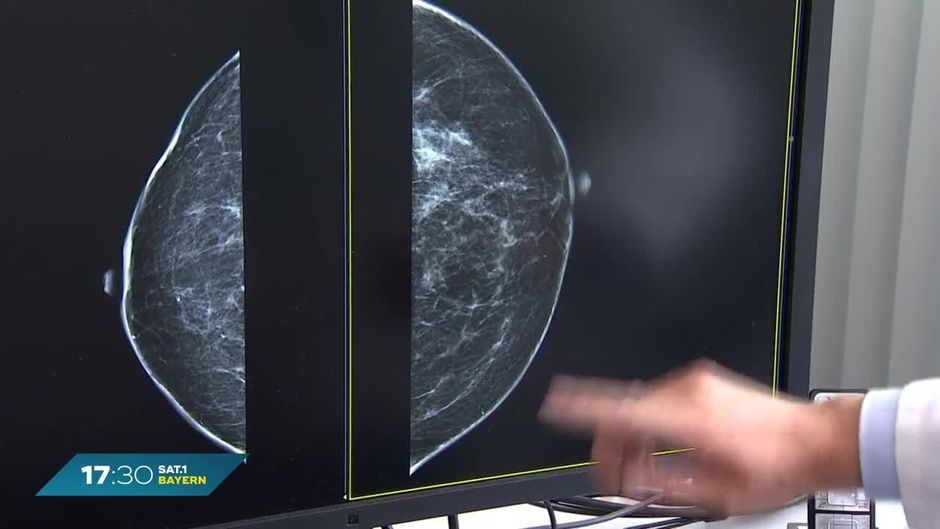

Jedes Jahr erkranken zehntausende Menschen in Deutschland an Brustkrebs. Besonders betroffen sind Frauen und deswegen können sie ab einem Alter von 50 Jahren alle zwei Jahre zur Mammografie gehen. Das Problem: Die Wartezeit für die Untersuchung beträgt bis zu acht Monate. Das ist der Grund.